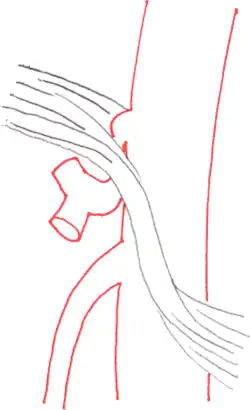

Das Ligamentum arcuatum medianum entspringt an der Basis des Zwerchfelles, dort wo der rechte und linke Zwerchfellschenkel (Crus dextrum et sinistrum) etwa in Höhe des 12. Brustwirbels zusammenkommen. Dieser Gewebebogen bildet die Vorderseite des Hiatus aorticus, durch den die Aorta mit dem Plexus aorticus abdominalis und der Ductus thoracicus ziehen.[2] Normalerweise sitzt das Ligamentum oberhalb des Abgangs des Truncus coeliacus, bei etwa 25 % der Menschen kreuzt das Ligament jedoch auf Höhe des Abgangs und engt dadurch die Arterie und benachbarte Strukturen, wie das Ganglion coeliacum ein. Bei einigen ist die Einengung so stark, dass die Krankheitssymptome entstehen.[1][3]

Die Befunde einer kurzstreckigen Einengung des Truncus coeliacus an seinem Abgang mit nachfolgender Erweiterung (poststenotische Dilatation), einer Einkerbung im oberen Aspekt des Truncus und eines hakenförmigen Verlaufes des Truncus unterstützen die Diagnose eines Truncus-coeliacus-Kompressionssyndroms.[1] Diese Bildkriterien sind in Exspiration betont und finden sich zum Teil sogar bei asymptomatischen Patienten, die nicht an dem Syndrom leiden.[1]

Auch müssen andere mögliche Differenzialdiagnosen bei einer abgangsnahen Einengung mit poststenotischer Dilatation, wie zum Beispiel arteriosklerotische Veränderungen, berücksichtigt werden.[1] Hier kann der hakenförmige Verlauf des Truncus coeliacus für die Unterscheidung hilfreich sein, wenn auch dieses Kriterium ebenfalls nicht pathognomonisch für das Truncus-coeliacus-Kompressionssyndrom ist. Die Häufigkeit für diese Anatomie bei normalen asymptomatischen Personen wird mit 10 bis 24 % angegeben.[1]